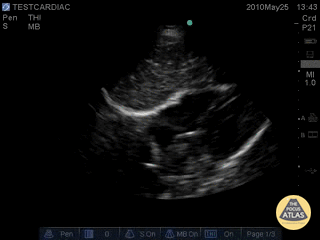

Normal Cardiac Anatomy - Normal Subcostal View